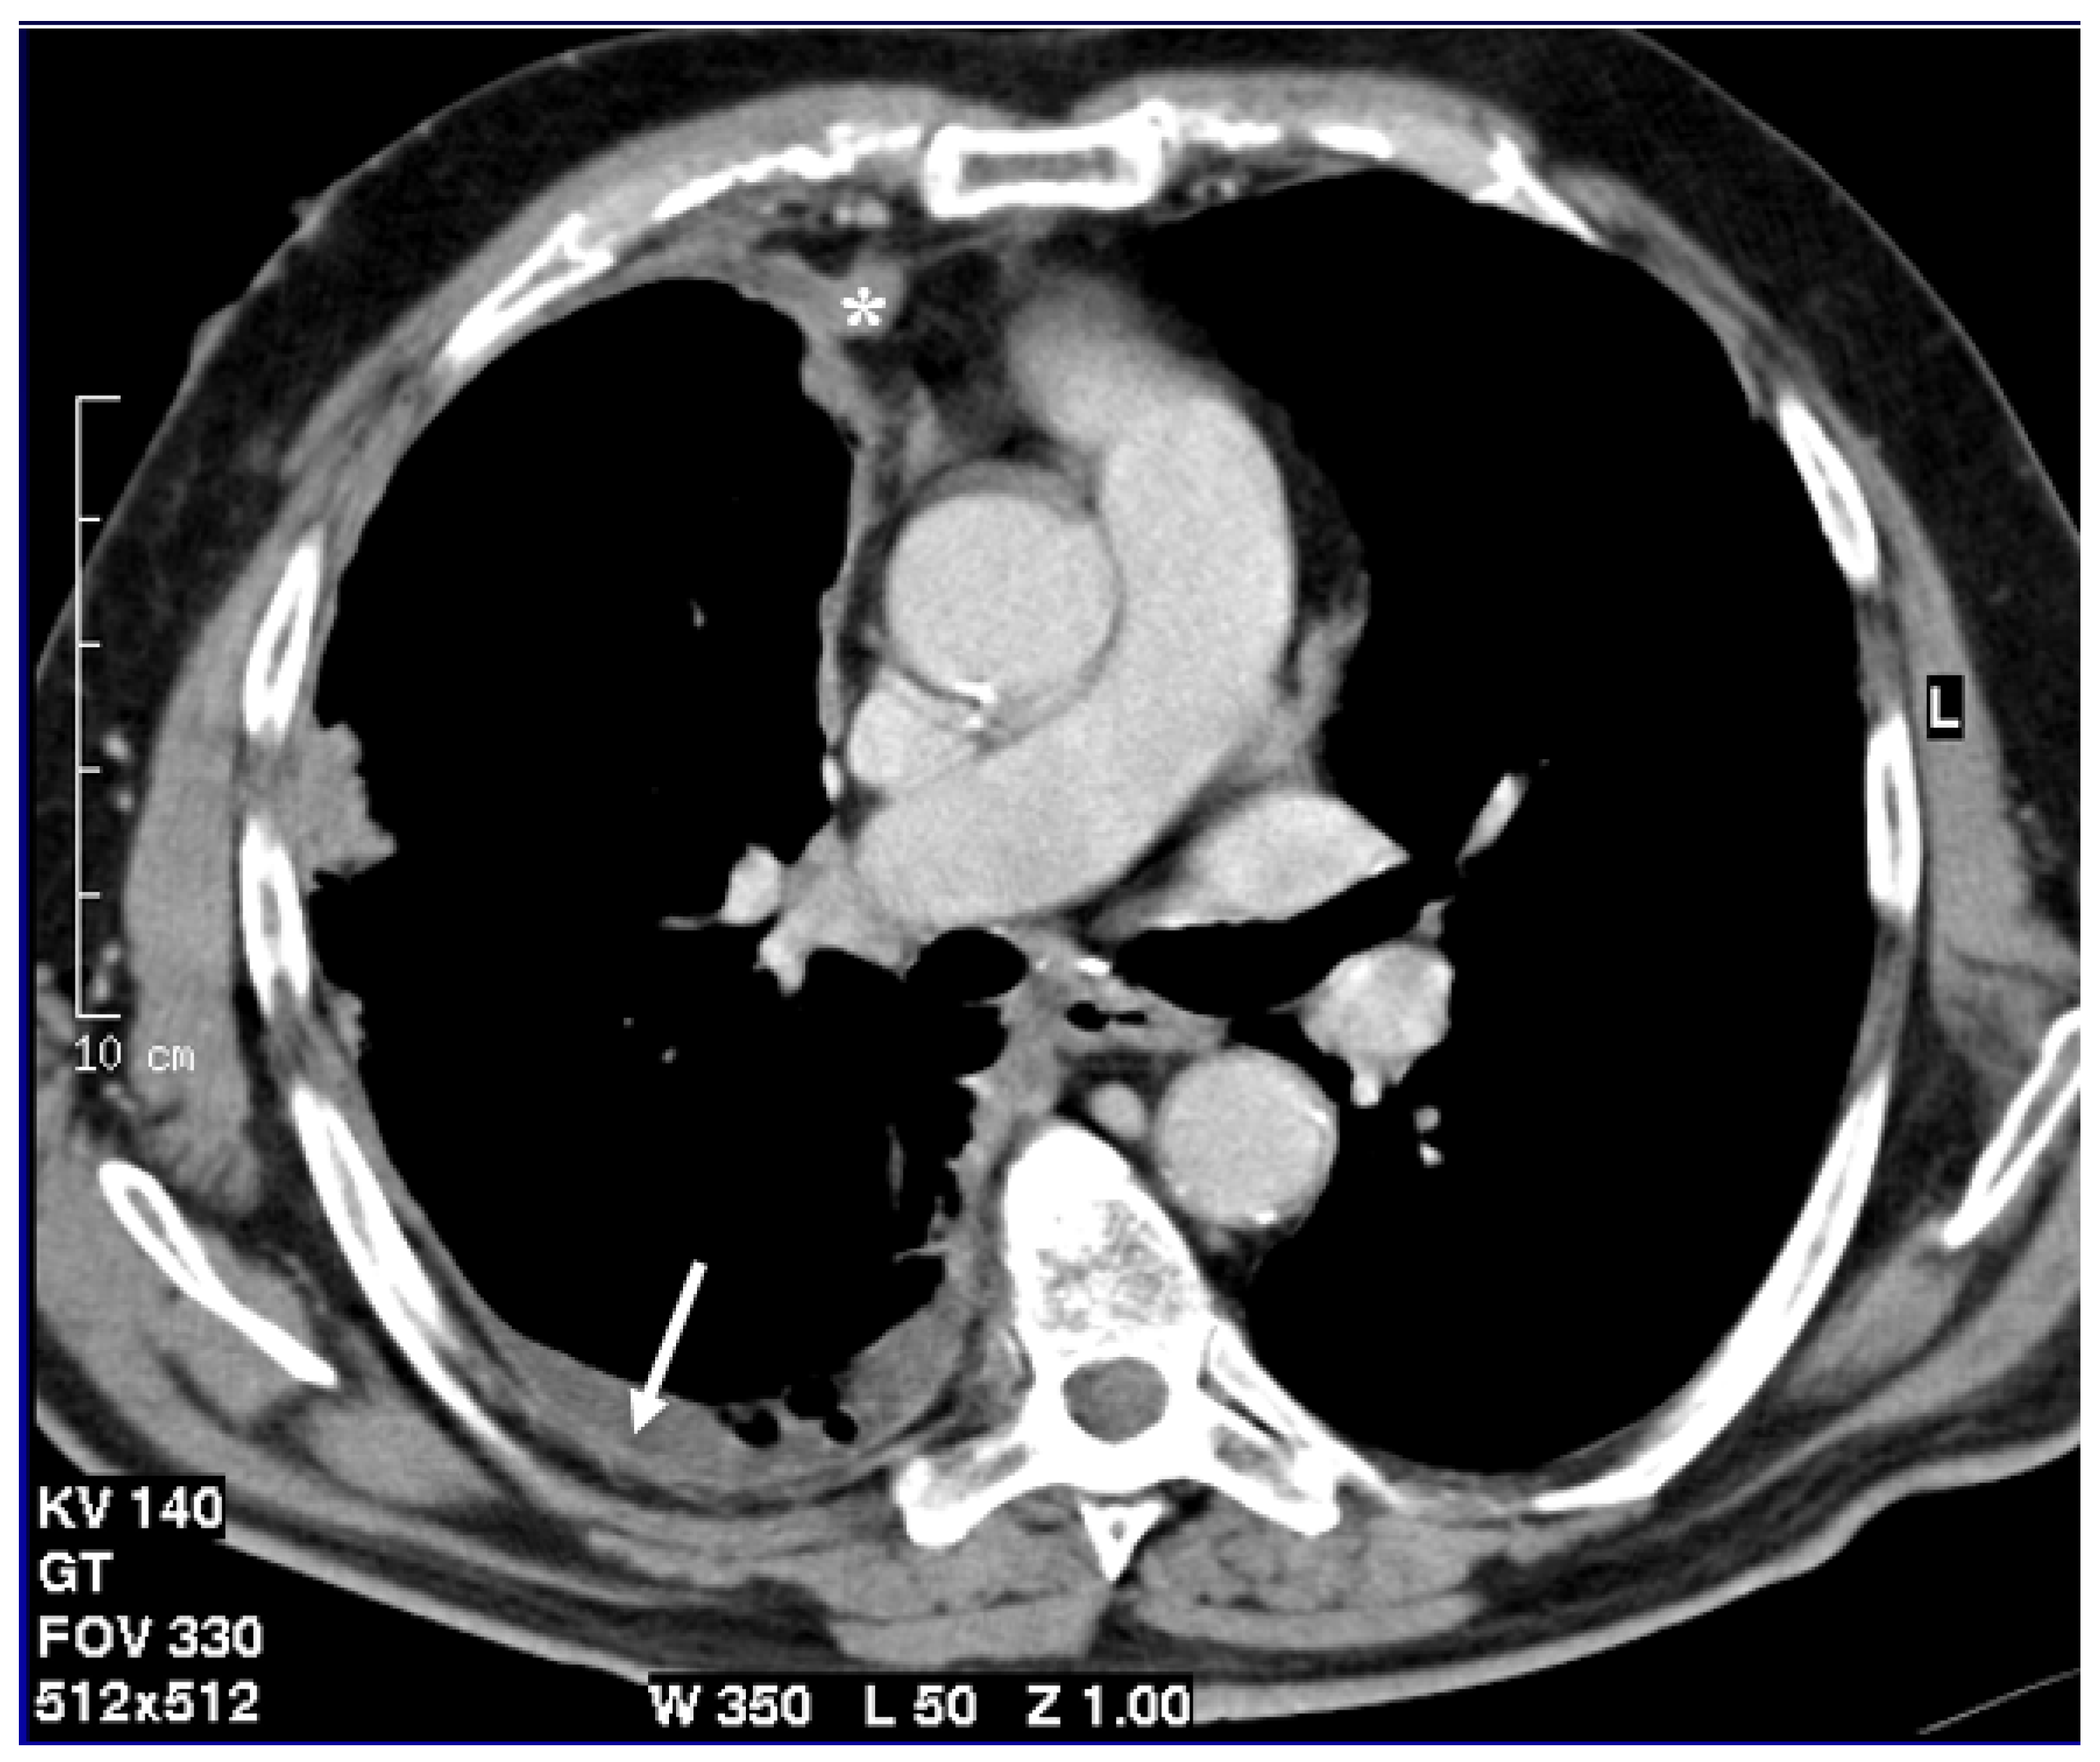

Figure 1.

Axial CT scan after contrast administration reconstructed with smooth kernel with mediastinal windows demonstrates circumferential pleural nodular thickening with mediastinal pleura involvement (asterisk) and pleural effusion (arrow).